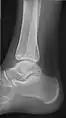

- Ankle - AP/Mortice and Lateral

Ankle - frontal

15 degrees internal rotation

Lateral (this one a bit suboptimal by not seeing straight through the ankle joint)

Lateral oblique (to visualize the posterior border of the tibia)